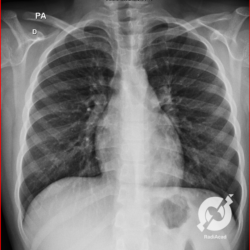

E o nome dado a esta alteração radiográfica que corresponde à substituição do ar alveolar por líquido é a consolidação alveolar.

Uma consolidação alveolar é, por definição, uma opacidade (imagem densa, branquinha) homogênea ou às vezes heterogênea (pela presença de calcificações ou cavidades), de limites mal definidos, exceto quando toca a pleura da parede ou das cissuras pulmonares. É um termo usado tanto em radiografia, como em tomografia computadorizada. Na tomografia, um outro termo é usado: vidro fosco, que é uma opacidade (branquinha mas não tanto como a consolidação), que borra o pulmão mas deixa ver os vasos de permeio (igual bigode de adolescente: dá pra ver todo o fundo).

Nós vamos mostrar aqui um pequeno apanhado de pneumonias de variados agentes, em diversos segmentos e lobos pulmonares, com extensões variadas. O objetivo é identificar o padrão radiológico de consolidação alveolar e não determinar o agente infeccioso, isso vai ser assunto para mais adiante. Aliás já antecipo que é fundamental saber localizar a lesão, porque alguns destes bichos gostam de determinados segmentos, alguns tumores também têm as suas preferências, então localização é fundamental. Se localização não fosse importante, um apartamento na beira do mar sairia o mesmo preço de um apartamento de frente pra BR-101, concordam?

Seguem alguns dos nossos casos de pneumonia para vocês treinarem os olhos e não se apavorarem nos plantões.